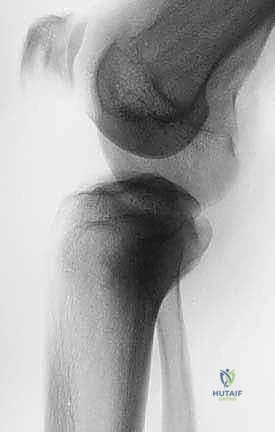

لفهم مدى تعقيد وعبقرية جراحة استئصال الظنبوب القريب، من الضروري الإبحار في أعماق التشريح الأساسي لهذه المنطقة الحيوية. لا يقتصر الأمر على مجرد عظام، بل هو نظام هندسي وبيولوجي متكامل ومعقد. يتكون مفصل الركبة من التقاء عظم الفخذ (Femur) من الأعلى، وعظم الساق أو الظنبوب (Tibia) من الأسفل، وعظم الشظية (Fibula) الجانبي، بالإضافة إلى الرضفة أو صابونة الركبة (Patella) في الأمام. الجزء القريب من الظنبوب هو الجزء العلوي العريض من عظم الساق، والذي يشكل القاعدة الأساسية التي يستند عليها مفصل الركبة ويتحمل وزن الجسم بأكمله.